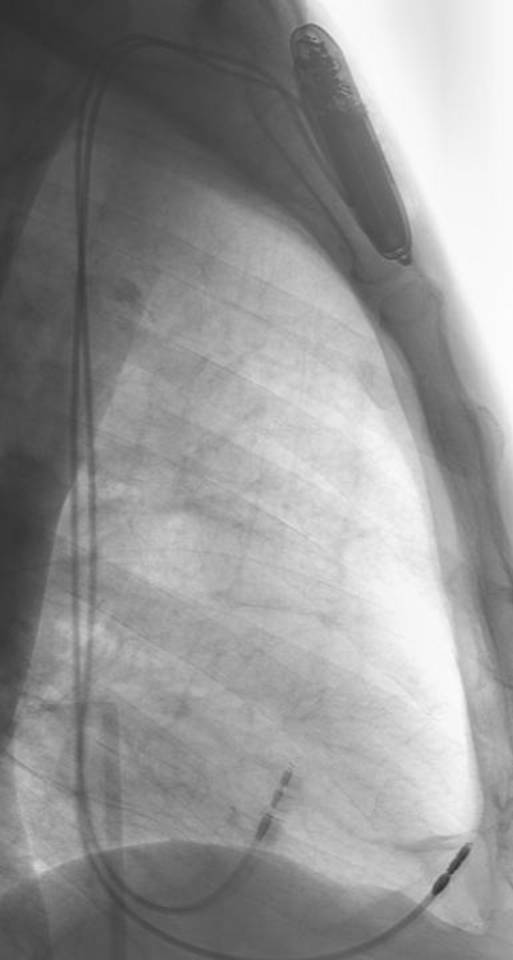

ペースメーカーは、BIOTRONIK社製、エヴィア(Evia DR-T電池寿命14年)に替わった。ホームモニターリングをし、ドイツにあるセンターへPMのロギングデータを夜中に毎日送る。MRIにも耐えるということだが、日本では承認されていない。

2012020201PM(植込み中のため、体外式ペーシング利リードもある)

2012021001PM

2012020202PM

2012020203PM